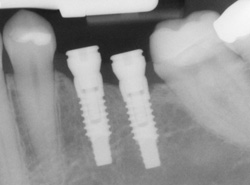

Single or Multiple Implants

Implants are versatile. If you are only missing one tooth, one implant plus one replacement tooth will do the trick. If you are missing several teeth in a row, a few strategically placed implants can support a permanent bridge (a set of replacement teeth). Similarly, if you have lost all of your teeth, a full bridge or full denture can be permanently fixed in your mouth with a strategic number of implants.

Computer Enhanced Treatment Planning We have special software on our computer that allows us to evaluate your dental CT scan in three dimensions for bone quality, bone quantity, and bone location to determine the best possible placement of your dental implants. This also allows us to work closely and smoothly with your restorative dentist to ensure an ideal result where your dental implants are concerned.